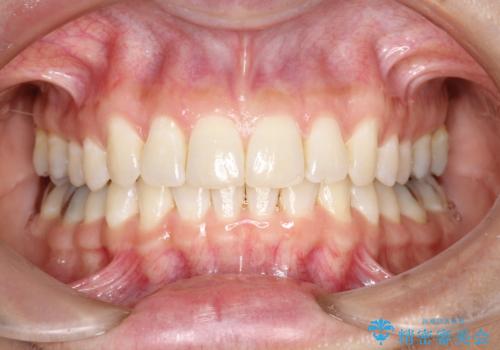

前歯のガタガタをインビザラインで矯正

- 前歯のがたつきを気にされて来院されました。

右上の前から2番目の歯が前方に大きく傾いており、下の前歯もガタガタしていました。

インビザラインにて、歯と歯のあいだをわずかに削り並べる計画としました。

しっかりとマウスピースを使用していただけたので、順調に治療を終えることができました